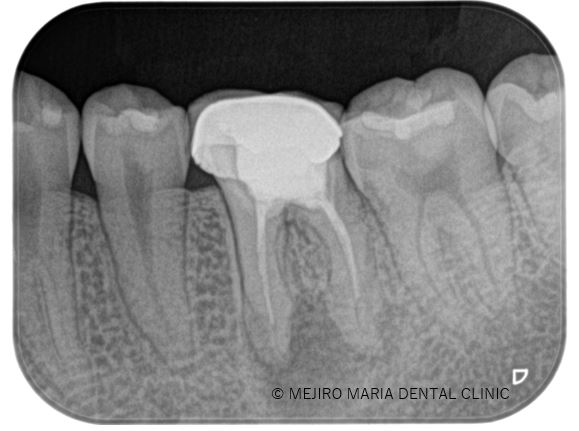

• 目白マリア歯科【症例】精密根管治療の費用対効果の考え方・再根管治療_治療前治療後のレントゲン画像比較

2022.05.24

【症例】精密根管治療の費用対効果をどう考えるか(再根管治療)